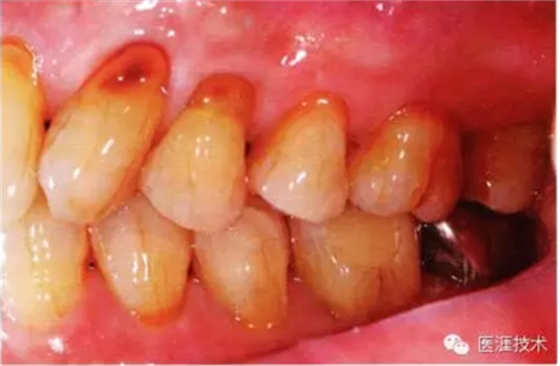

44歲牙周炎女性的臨床照片

44歲患有糖尿病病史(未治愈)。菌斑控制不良。通過牙周探診,全頜有4~8mm的牙周袋,在X光片中可以看到上頜前牙處中度牙槽骨吸收,磨牙處重度牙槽骨吸收。二次齲齒和根面齲齒也有發(fā)生??梢钥吹礁∧[性腫脹,收到刺激后會出血。